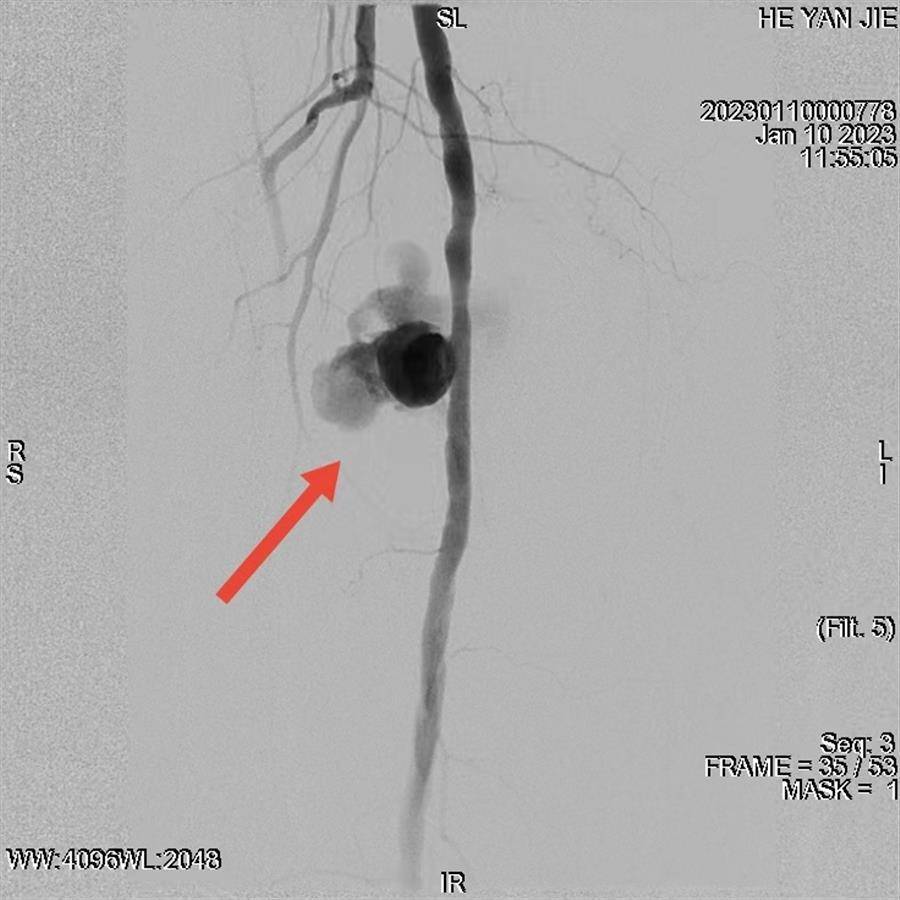

假性动脉瘤瘤体最长径达到10cm,为少见的巨大假性动脉瘤

经过充分的术前准备,骨科、介入放射科、肾病内科、手术麻醉中心等多学科共同参与了手术。手术中,介入放射科副主任医师严子才发现,由于破口较大,导引导丝非常容易进入假性动脉瘤内。最后经过调整和精确修剪“开窗”,导丝和支架输送装置顺利到位,释放后完美隔绝瘤腔,成功封堵了假性动脉瘤。随后,手术麻醉中心秦智刚主任立即为患者麻醉,骨科姚士军主任主刀行微创骨折复位内固定术,期间肾病内科随时准备为患者进行透析。最终,在各方共同努力下,多学科协作的接力手术顺利完成。目前,何婆婆的术后恢复良好。